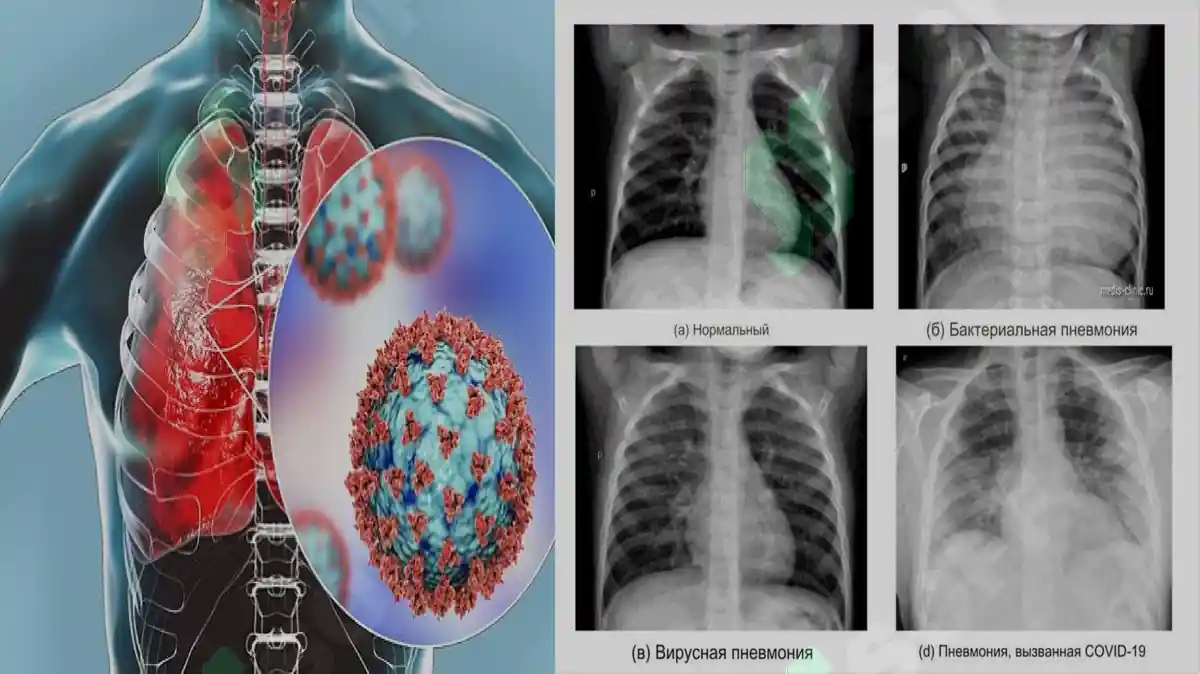

Ushbu taqdimotda pnevmoniya (zotiljam) kasalligi, uning turlari, kelib chiqish sabablari va diagnostikasi yoritilgan. Shuningdek, kasallikni boshqarishda gospital pedagogikaning vazifalari batafsil bayon etilgan. O'pka to'qimalarini zararlaydigan bu infeksion kasallik haqida keng ma'lumotlar berilgan.